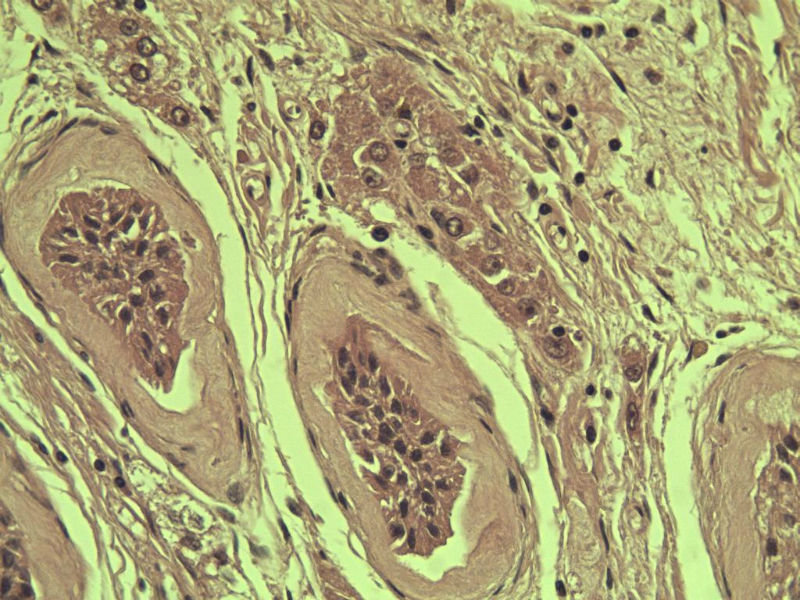

腹腔隐睾图3

名称:图3

描述:a212.Jpg.jpg